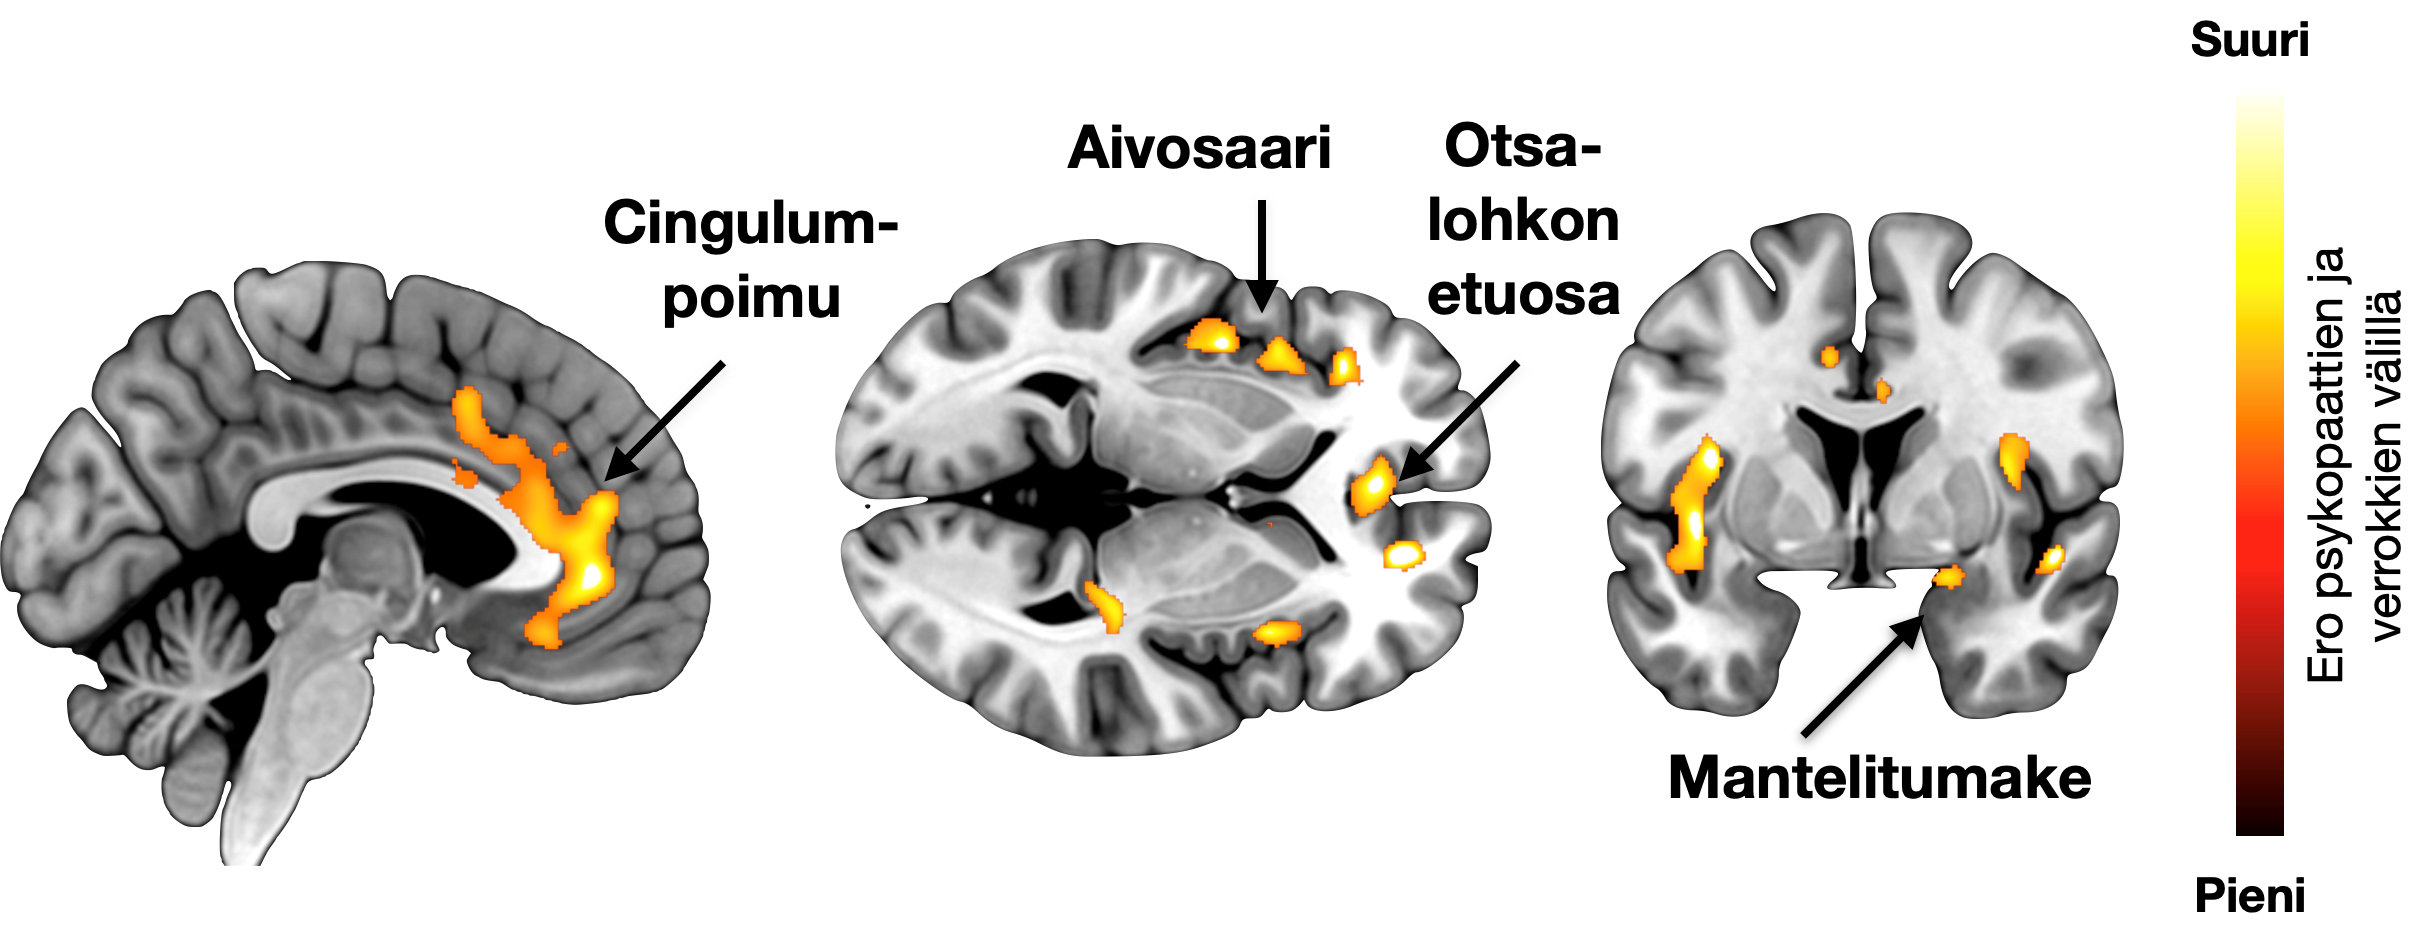

Kuvassa aivojen alueet, joiden tiheys oli alentunutta psykopaateilla.

– Havaitsimme, että psykopaattisilla väkivaltarikollisilla aivojen toiminnanohjaukseen ja tunteiden säätelyyn osallistuvien aivojen alueiden tiheys on alentunut. Väkivaltaisia elokuvia katseltaessa nämä alueet puolestaan reagoivat voimakkaammin psykopaateilla. Myös kontrolliaineistossa havaittiin samanlaisia muutoksia. Mitä enemmän ihmisillä oli psykopatiaan liittyviä piirteitä, sitä enemmän heidän aivonsa muistuttivat psykopaattisten rikollisten aivoja, kertoo professori Lauri Nummenmaa Turun PET-keskuksesta.

– Muutoksia näkyi erityisesti aivojen alueilla, jotka osallistuvat tunteiden kokemiseen ja säätelyyn. Näiden alueiden toiminnan ja rakenteen muutokset voivat olla psykopatiaan liittyvän tunnekylmyyden ja impulsiivisuuden taustalla, sanoo professori Jari Tiihonen Karoliinisesta instituutista.